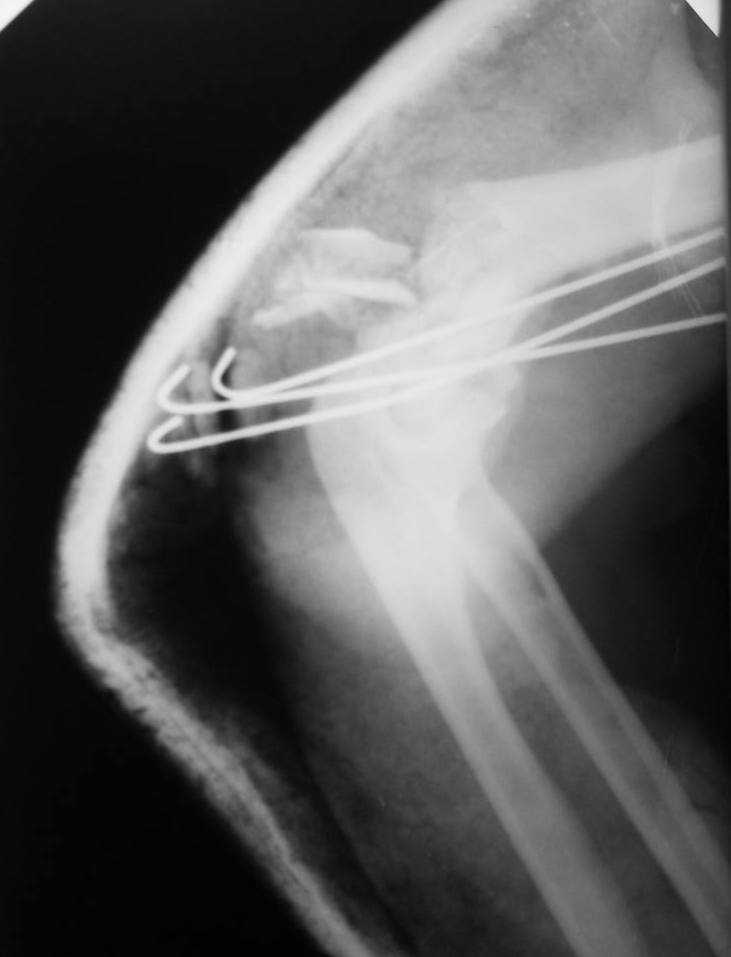

больная Ч. 24 года. Поступила в отделение после ДТП 15.01.08 при поступлении о/с костей таза АВФ. О/с лев плечевой кости спицами. На данный момент состояние больной ближе к удовлетворительному. С переломом костей голени особых вопросов нет. Хотелось бы услышать ваше мнение.